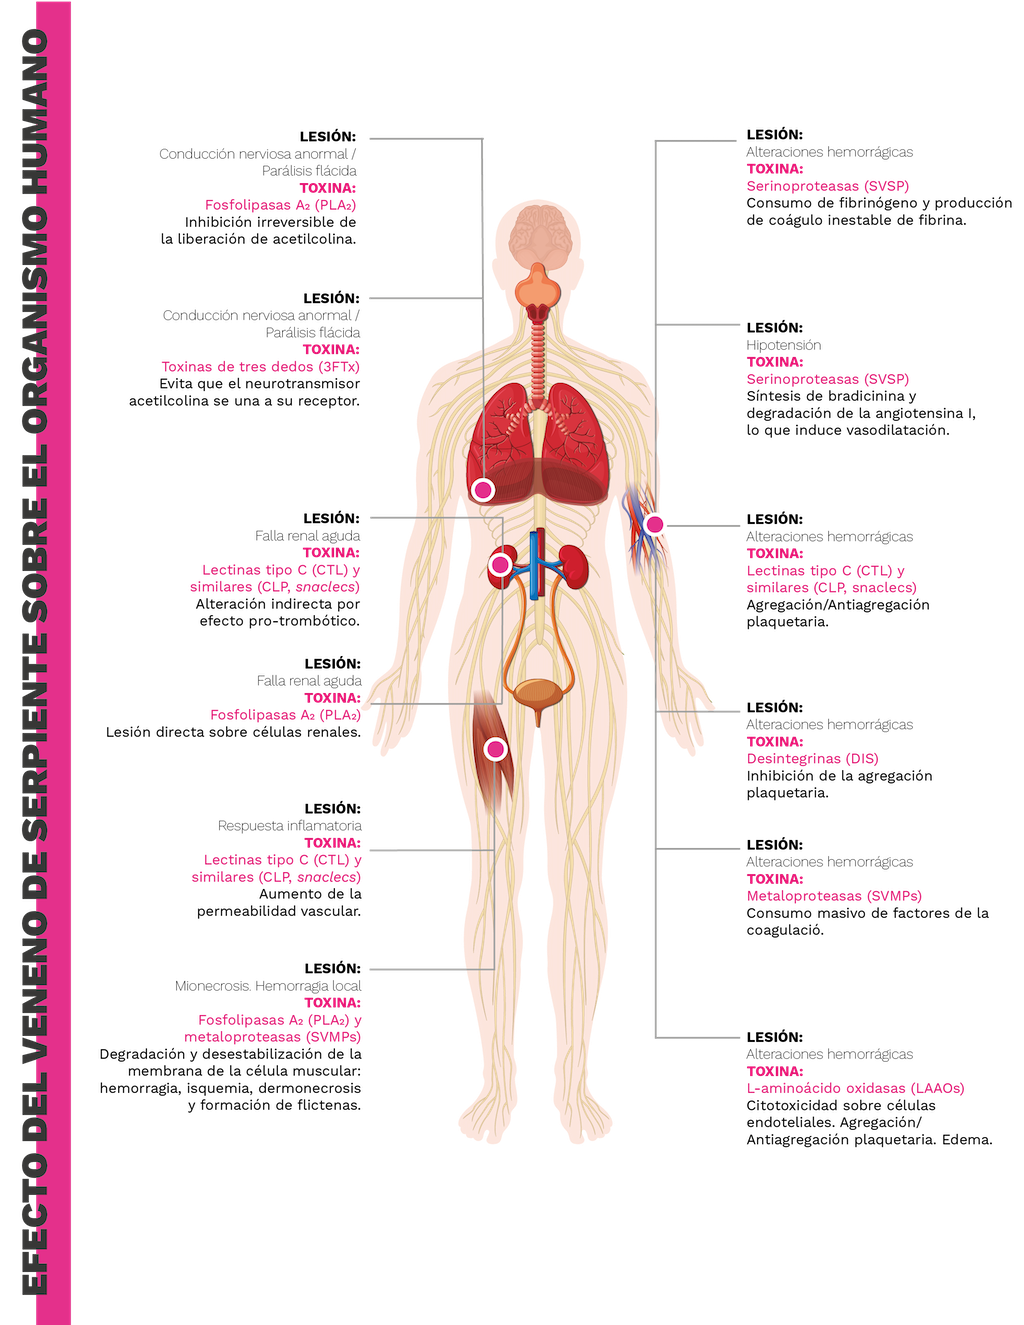

Los venenos de serpientes de la familia Elapidae son principalmente neurotóxicos, mientras que los de la familia Viperidae inducen coagulopatías, hemorragias y daños tisulares locales [25,26]. Esto se debe a la prevalencia de las proteínas 3FTx y PLA2 en el veneno de elápidos que pueden causar debilidad similar a la miastenia gravis [27]. Esta debilidad puede afectar a cualquier músculo; y si el bloqueo neuromuscular afecta a los músculos de la respiración, puede provocar la muerte [26,27]. Por otro lado, el veneno de vipéridos tiene efectos principalmente hemotóxicos y miotóxicos. Los agentes identificados en el veneno de las víboras incluyen proteinasas similares a la trombina que provocan coagulopatía [28], hialuronidasas que alteran las matrices extracelulares, fosfolipasas A2 que causan inflamación local y dolor [29], y metaloproteasas que contribuyen a la hemorragia [30,31]. El resultado es una destrucción local del tejido empeorada por el efecto coagulopático [26].

Las serpientes venenosas emplean las fosfolipasas A2 (PLA2) para provocar mionecrosis (muerte de células musculares), neurotoxicidad (parálisis de los músculos respiratorios), inflamación, dolor y alteración de la coagulación sanguínea. Todos estos efectos contribuyen a la inmovilización de la presa y pueden observarse en accidentes ofídicos.

Neurotoxicidad